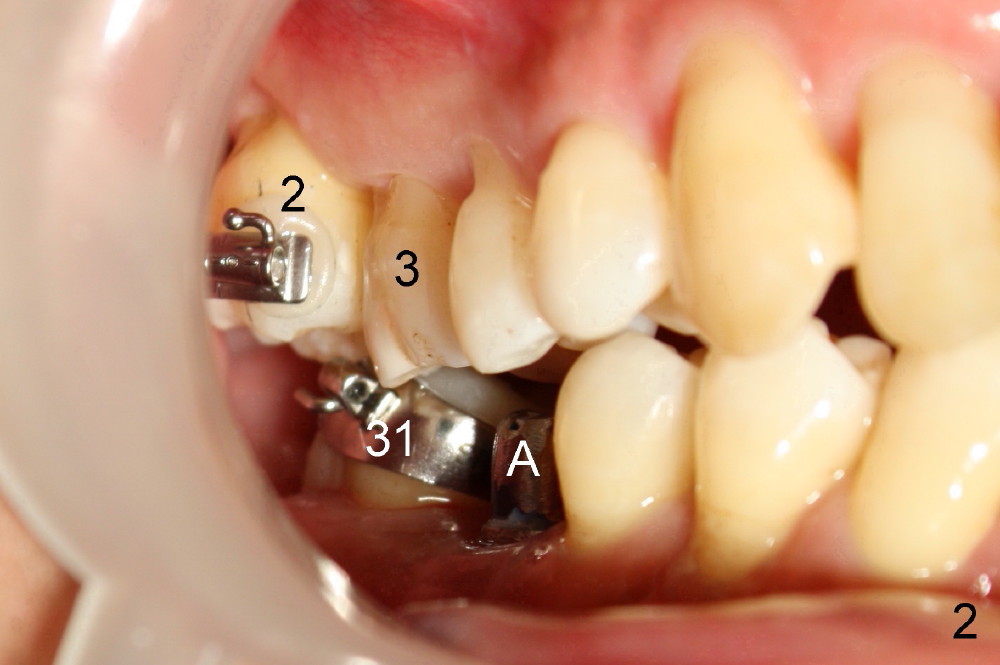

A 50-year-old man has lost the lower right 1st molar for several years (Fig.1: 30). The 2nd molar has shifted (arrow) and inclined (white line) mesially. It does not appear to occlude with the tooth #2 in this panoramic X-ray. It is planned to place an implant at the site of #30 and after osteointegration to use it as an anchorage to upright and distalize the tooth #31. Four and a half months after placement of a Tatum tapered implant (6x17 mm), a 5 mm 10 degree unipost ((short) abutment) is placed and prepared for temporary crown (Fig.2: A). Severe cross bite (overjet) is noted between the teeth #2 and 31. It is due to combination of the lingual inclination of the tooth #31 (Fig.3 (mirror view) arrow) and the buccal displacement of the tooth #2 (Fig.4 mirror image).